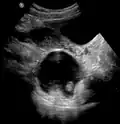

Large ovarian cyst

A complex cyst due to a dermoid as seen on ultrasound -